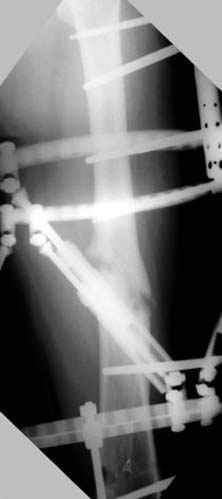

Djoldas Kuldjanov 23 Ноябрь 2004, 18:21

пластическая модель; и коррекция бедра аппаратом Илизарова.

хотя даже если бы и инфекция , то nail exchange с рассверливанием канала - вариант дебрайдмента) Я думаю, что последовательность развития событий:

Узкий к-м канал - тонкий гвоздь- усталостный перелом дистальных винтов - развитие нестабильности и как ее результат остеолиз вокруг гвоздя - деформация анатомической оси бедра. Похоже, что я понял почему аппарат, а не новый гвоздь:-)

ЕТ - Изначально костно-мозговой канал бедра был узкий, дальнейшее его рассверливание ещё больше скомпрометирует прочность бедра( латеральный кортекс дистального отломка уже истончен), приведет к дефекту наружной стенки - хотя это только мои догадки - хотелось бы знать мнение Джолдаса о выбранной тактике.